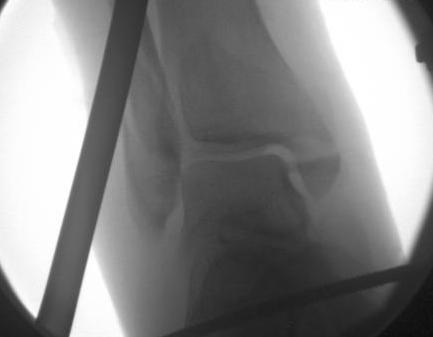

Indirect reduction and AP screws

1. Indirect reduction and AP screws - small fragment that can be reduced